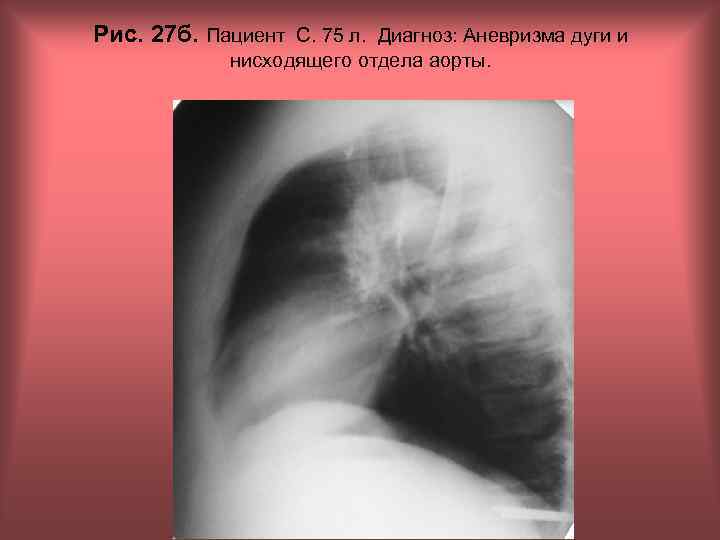

Рис. 27 а. Пациент С. 75 л. Диагноз: Аневризма дуги и нисходящего отдела аорты. Н. С. Воротынцева, С. С. Гольев Рентгенопульмонология

Рис. 27 б. Пациент С. 75 л. Диагноз: Аневризма дуги и нисходящего отдела аорты. Н. С. Воротынцева, С. С. Гольев Рентгенопульмонология